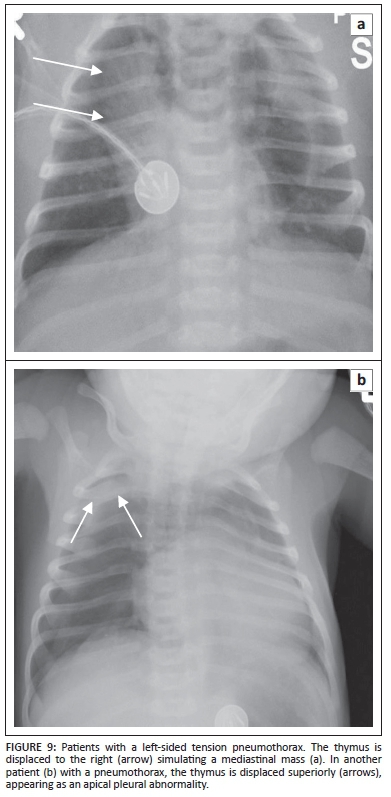

Prominence of one or more lobes can simulate cardiomegaly on frontal radiography (Figure 8) that can, however, be seen to be thymus on the lateral radiograph. Normal thymus may obscure or simulate upper lobe pneumonia (Figure 7).4,7,8 Sometimes the presence of other pathologies may cause the thymus to appear abnormal, as seen in pneumomediastinum or pneumothorax where the thymus has been likened to 'angel's wings' or 'spinnaker sail' (Figure 8). Pneumothorax, when under tension, may cause displacement of the thymus, disguising it as an abnormality (Figure 9).